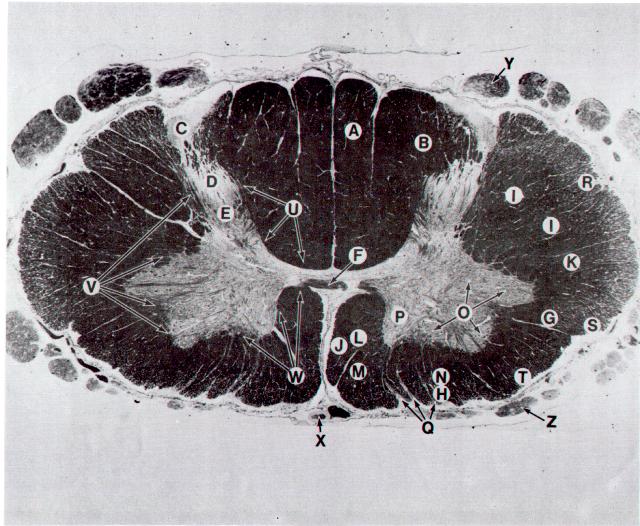

Plate IV. Spinal cord at the level of the cervical enlargement

A. Gracile fasciculus

B. Cuneate fasciculus

C. Dorsolateral fasciculus (Lissauer's tract)

D. Substantia gelatinosa

E. Posterior funicular gray (nucleus proprius)

F. Anterior white commissure

G. Lateral spinothalamic tract

H. Anterior spinothalamic tract

I. Lateral corticospinal tract

J. Anterior corticospinal tract

K. Rubrospinal tract

L. Medial longitudinal fasciculus

M. Tectospinal tract

N. Lateral vestibulospinal tract

O. Lateral motor nuclei

P. Medial motor nuclei

Q. Fascicles of vertral root of spinal nerve

R. Dorsal spinocerebellar tract

S. Ventral spinocerebellar tract

T. Spino-olivary tract

U. Posterior propriospinal tract

V. Lateral propriospinal tract

W. Anterior propriospinal tract

X. Anterior spinal tract

Y. Dorsal root of spinal nerve

Z. Ventral root of spinal nerve